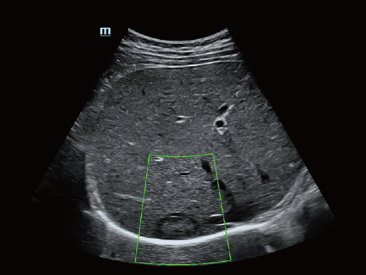

Dank der ZONE Sonography?-Technologie (ZST+) wird das B-Bild des Resona 7 ├╝ber die komplette Tiefe fokussiert, sodass keine Fokuspunkte mehr gesetzt werden m├╝ssen. Die Schall-Lauf-Geschwindigkeit (SSC) wird auf Knopfdruck individuell auf den Patienten angepasst, was die Darstellung von Organen, Grenzfl?chen und Gewebever?nderungen erheblich verbessert. Und dank der fortschrittlichen iFusion-Funktion k?nnen optional die Daten von Ultraschall-, MRT-und CT-Bildern synchronisiert werden.